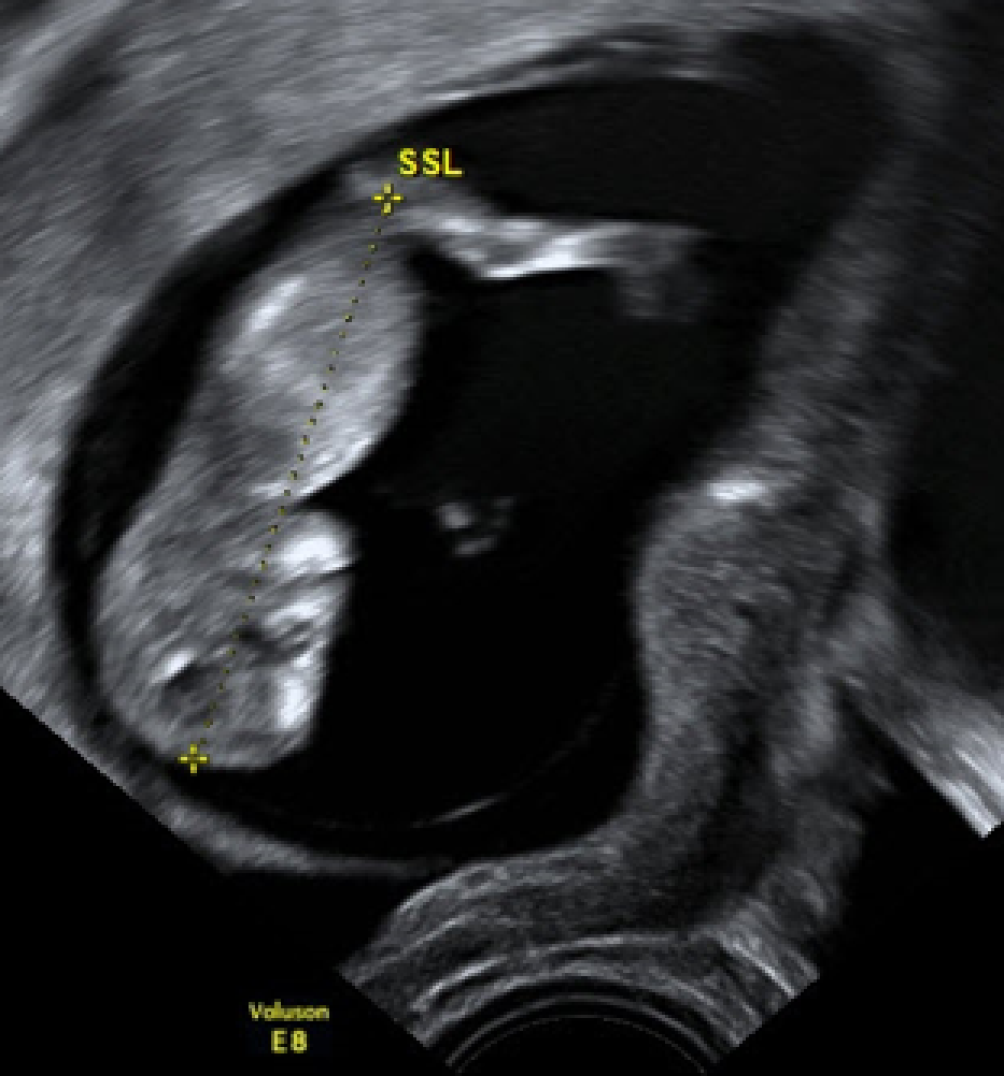

Ein 3‑D-Schall ist schön, die darin abgegriffenen Messstrecken sind allerdings wesentlich ungenauer als die von B‑Mode-Aufnahmen (Abb. 3 und 4).

Abb. 4

Selber Embryo wie in Abb. 4 im Zuge derselben Untersuchung. 3‑D ist optisch wesentlich anschaulicher als B‑Mode, allerdings bei Einbringen der Messstrecken wesentlich ungenauer

Bild vergrößern